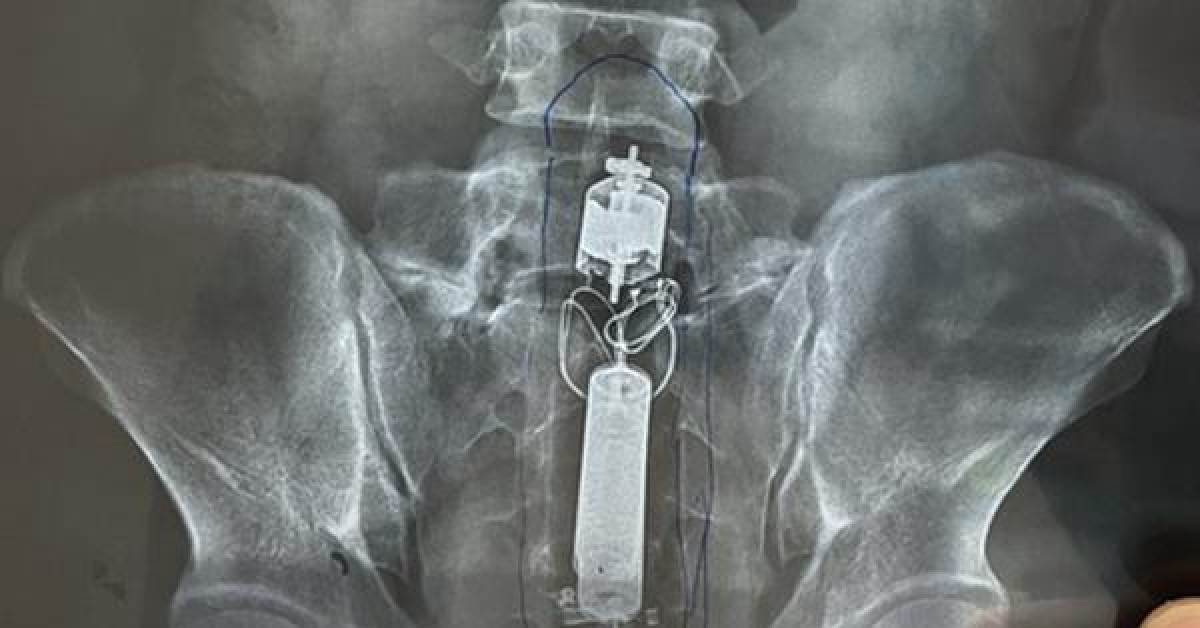

Tại bệnh viện, bệnh nhân được nội soi trực tràng. Các bác sĩ xác định quả dưa leo dài hơn 10 cm nằm sâu trong lòng trực tràng. Tuy nhiên, do kích thước qủa dưa quá lớn, tiến hành gắp qua nội soi thất bại nên các bác sĩ quyết định phẩu thuật cho bệnh nhân.

Dị vật là quả dưa leo dài hơn 10cm được lấy ra ngoài. (Ảnh: BV cung cấp)